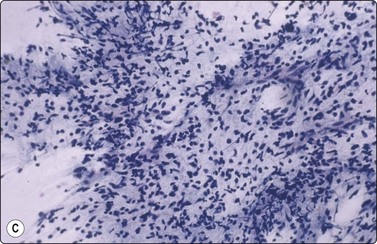

Seminoma (Figs 13.30 and 13.31)14,50,57-63,65,66

image image

Fig. 13.30 Seminoma

(A) Dispersed cells with large pale nuclei and poorly defined cytoplasm; note ‘tigroid’ background, smudged nuclei and small lymphocytes (MGG, HP); (B) Dispersed cells; moderately pleomorphic vesicular nuclei; single or multiple prominent nucleoli; many scattered lymphocytes (Pap, HP).

Criteria for diagnosis

Cell-rich smears,

Dispersed cells, little tendency to clustering,

Highly fragile cytoplasm and nuclei (’tigroid background’ (TB) and nuclear trailing),

Large rounded vesicular nuclei; distinct nucleoli, smaller than in embryonal carcinoma,

Irregular chromatin with some clearing,

Abundant fragile, pale/clear cytoplasm; some marginal vacuoles (punched-out vacuoles),

Lymphocytes, plasma cells,

Tangled chromatin threads (seminoma cells and lymphocytes),

Some epithelioid histiocytes, epithelioid granulomas (variable),

Striking contrast in size between seminoma cells and the background of lymphocytes and plasma cells.

Immunocytochemistry: cells positive for PLAP, c-kit (CD117) and OCT 3/4, and negative for CD30, AE1/AE3, and CK7, CK8, CK18 and CK19, although focal pancytokeratin-positive cells may be seen.

Seminoma is a highly cellular neoplasm of poorly cohesive cells and little stroma. The presence of a lace-like tigroid background (TB), and the high cellularity including lymphocytes account for the intense navy-blue color of the smears. This may suggest the diagnosis even before microscopic study. Comments about the origin of TB and the distinction from ‘lymphoglandular bodies’ have been made elsewhere.60 TB may go unnoticed in Pap-stained smears, but is more conspicuous in DQ smears (Fig. 13.30). A diagnosis of seminoma should not be based solely on the presence of TB or TB-like material. We have observed TB-like material also in aspirates of embryonal carcinoma. The contrary is also true: seminoma should not be ruled out simply because the pathologist is unable to identify TB.14 Large seminomas may show prominent necrosis. Necrosis is a major cause of false negatives in testicular FNA.59 Tumor giant cells or syncytiotrophoblastic cells may be seen in aspirates of seminoma, but can also be found in embryonal carcinoma, mixed TGCT and in trophoblastic tumors.